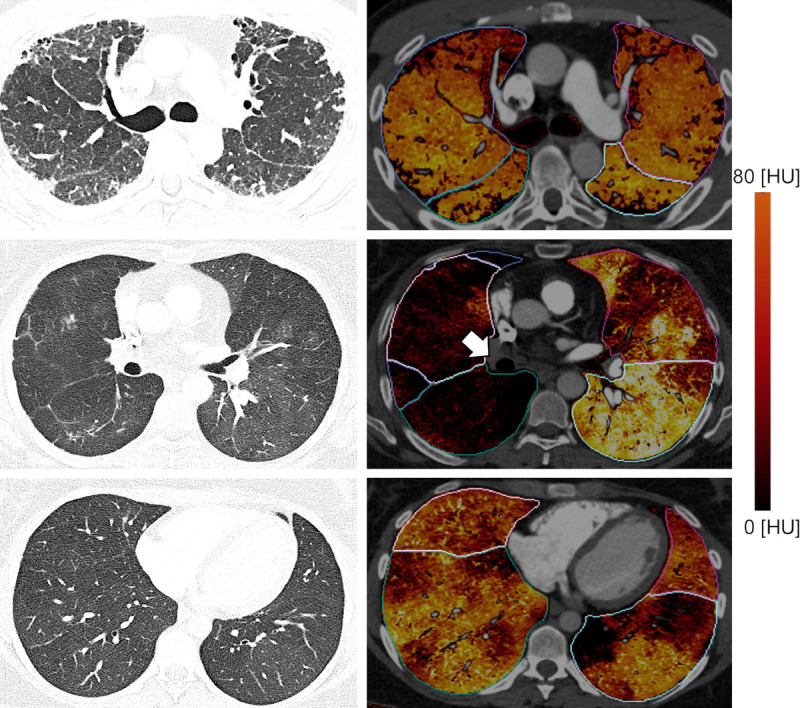

Objectives: The aim of this study was to evaluate the feasibility and efficacy of chronic pulmonary thromboembolism assessment using photon-counting detector computed tomography (PCD-CT) iodine maps of the lung parenchyma.

Materials and methods: This institutional review board-approved retrospective study included 83 subjects (49.4% male, aged 62.4 ± 13.4 years; 50.6% female, aged 59.9 ± 17.1 years) who underwent clinically indicated PCD-CT scan to rule out chronic thromboembolic pulmonary hypertension (CTEPH). Two blinded readers used iodine maps and corresponding sharp-kernel CT reconstructions in the lung window to evaluate perfusion defects and identify patients with chronic pulmonary thromboembolism (CTEPH, CTEPH overlap with other causes of pulmonary hypertension [PH], chronic thromboembolic disease [CTED]). No other clinical or imaging information was given. Discordance was resolved in a subsequent consensus read. The clinical diagnosis was reviewed in an interdisciplinary clinical setting. The accuracy, sensitivity, and specificity of radiologic evaluation and clinical diagnosis were calculated.

Results: Of the 83 subjects included, 32 were diagnosed with CTEPH, CTEPH overlap, or CTED, 35 were diagnosed with PH caused by other pathologic mechanisms, 10 had no PH, and 6 had suffered previous acute pulmonary embolism, which resolved. The interreader agreement was good (Cohen κ = 0.74). The consensus reached high accuracy (0.88), sensitivity (0.94), and specificity (0.84), as well as good agreement with interdisciplinary clinical diagnosis (Cohen κ = 0.75). No cases with confirmed CTEPH as the primary cause of PH or CTED were missed. Patients with pulmonary arterial hypertension were most frequently rated false-positive. The mean effective dose (±standard deviation) was 1.3 (±0.76) mSv.

Conclusions: Accurate, sensitive, and specific diagnosis of pulmonary chronic thromboembolism at low radiation dose is possible using iodine maps reconstructed from PCD-CT scans.